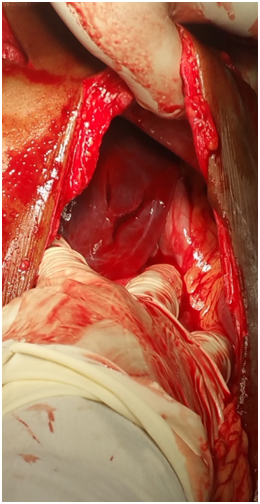

The Thoracotomy and Laparotomy procedures were done. Intraoperative findings were as follows: The patient had a collapsed left lung, There was a penetrating wound in the pericardium in the right heart ventricle. The Sternum was ripped apart and the pericardial tamponade was found and Pericardial opening had to be done. The Penetrated hears was shooting the heart blood out. The stabbed heart was sutured. The abdominal stub wound revealed a tear in the stomach and a linear laceration on the left lobe of the liver. These were repaired.

Figure 3 Stabbed heart.

Figure 5 Identifying stab on heart.